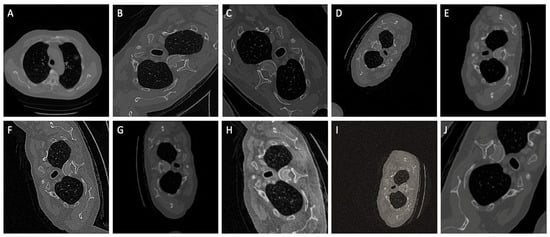

3.1. Dataset